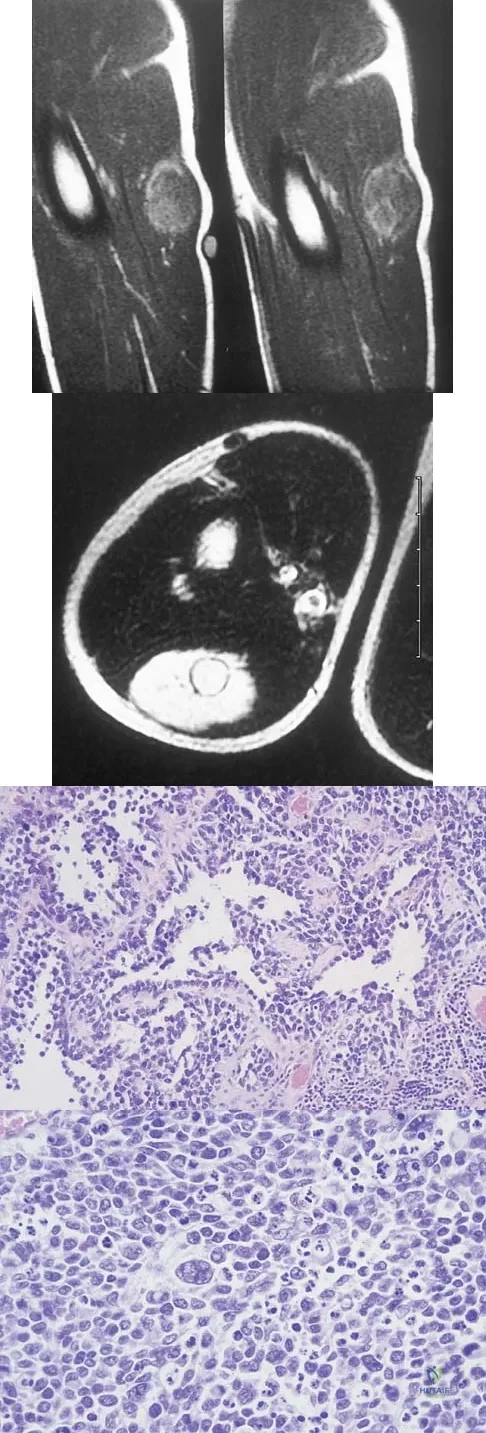

Question 18

A 13-year-old girl has had increasing left hip pain for the past 4 months. A radiograph, bone scan, MRI scan, and photomicrograph are shown in Figures 1a through 1d. Which of the following immunohistochemistry results would confirm the most likely diagnosis?

Explanation